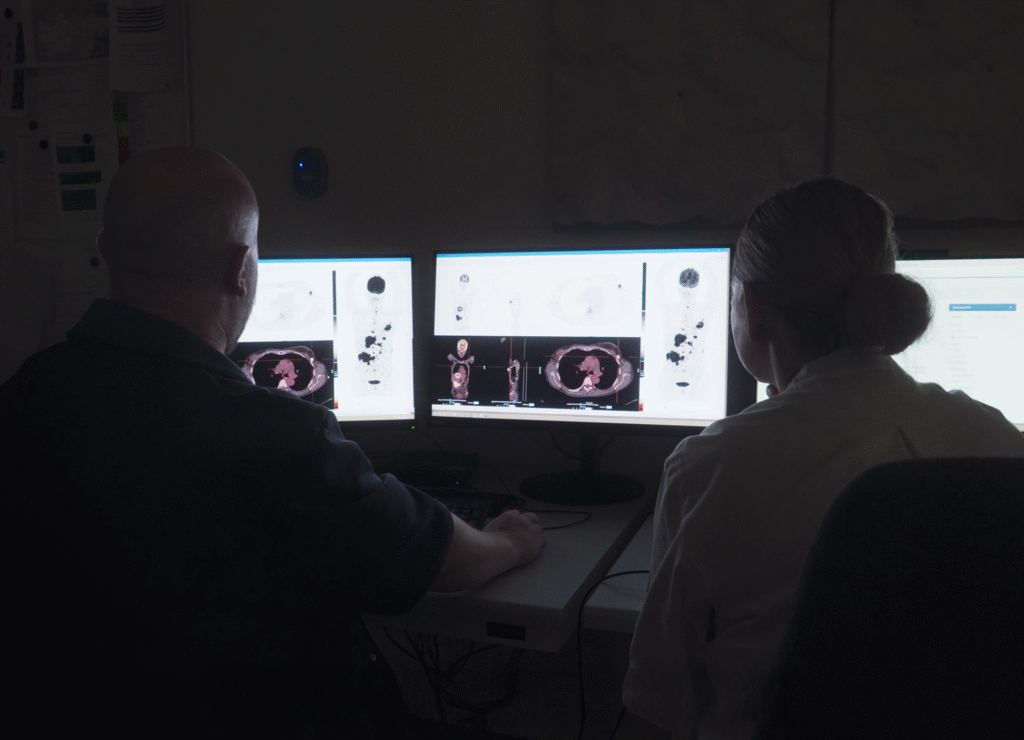

NoloSight’s ProPET is an advanced probabilistic reconstruction and image analysis methodology specifically designed to enhance lesion detection in PET/CT imaging. By combining informed prior models with machine learning, ProPET improves the ability to identify small lesions while maintaining clinical accuracy.

Enhanced Lesion Detection

Improved Diagnostic Confidence

Seamless Clinical Integration